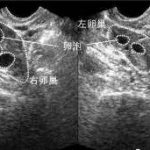

那么邵阳第三代试管到底有多高的成功率呢?首先需要明确,试管婴儿的成功率和多种因素有关,包括女方年龄、男方精子质量、卵子质量等等。因此在进行邵阳第三代试管前,医生需要对每个夫妇进行详细评估,并制定个性化的治疗方案。

据医疗机构统计数据显示,全国范围内平均每5组接受邵阳第三代试管治疗就能够实现1组生育成功。在这些数据中,有些夫妇可能在一次尝试中就取得了好结果;而另一些人则可能需要进行多次尝试才能成功。因此邵阳第三代试管的成功率并不是固定的数字,需要根据不同情况进行评估。

除了以上因素外,夫妇双方的身体健康状况、治疗过程中是否遵循医生的指导等也会对试管婴儿的成功率产生影响。此外邵阳市的医疗机构在技术水平和设备设施上都处于较高水平,在这些条件下进行试管婴儿治疗也有助于提高成功率。